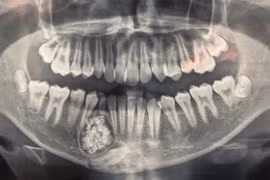

Bệnh viện Đa khoa tỉnh Khánh Hòa cho biết các bác sĩ vừa thực hiện ca phẫu thuật, lấy ra gần 100 cái răng trong khối u hàm dưới của 1 bệnh nhân 13 tuổi.